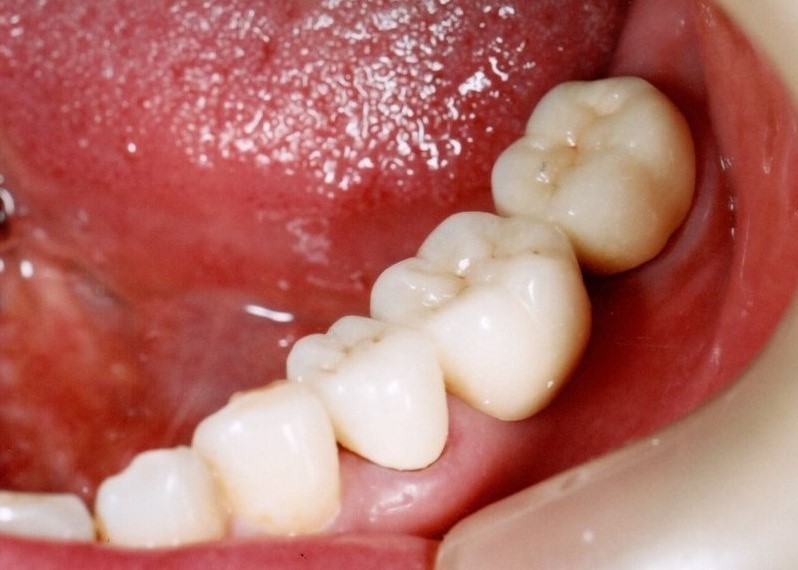

奥歯インプラント(スクリュー固定)

(伊東市 女性)

治療の流れ

むし歯で歯を失ってしまいました。

インプラントを埋入し、最終的な被せ物を装着しました。(ネジ穴をふさぐ前)

ネジ穴をふさぐとこの様な状態になります。

インプラント手術:250,000円

静脈内鎮静法:0円

既製アバットメント:90,000円

メタルボンド:130,000円

総額:470,000円+税